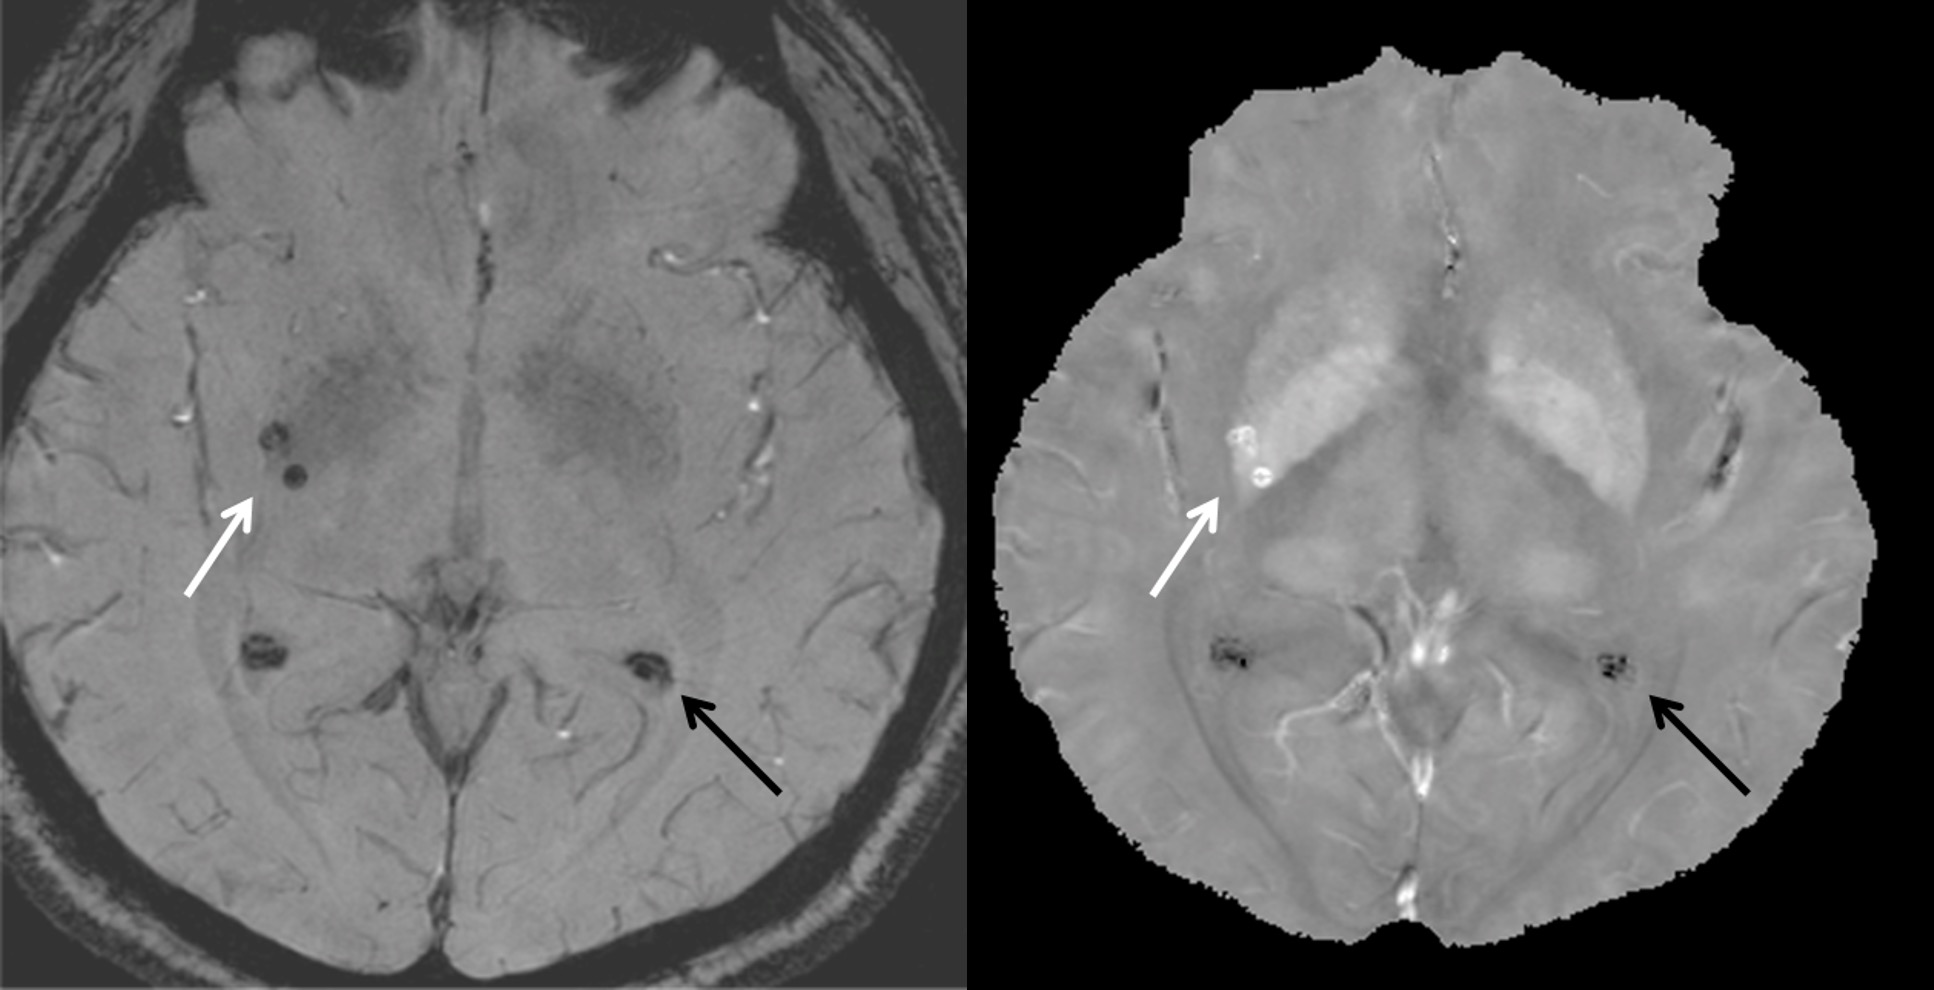

Traditional T2* weighted gradient echo magnitude or susceptibility weighted imaging (SWI) images (left) display both calcifications and hemorrhages with indistinguishable hypointensity. QSM (right) displays calcifications with negative values (dark arrow) and hemorrhages with positive values (white arrow).